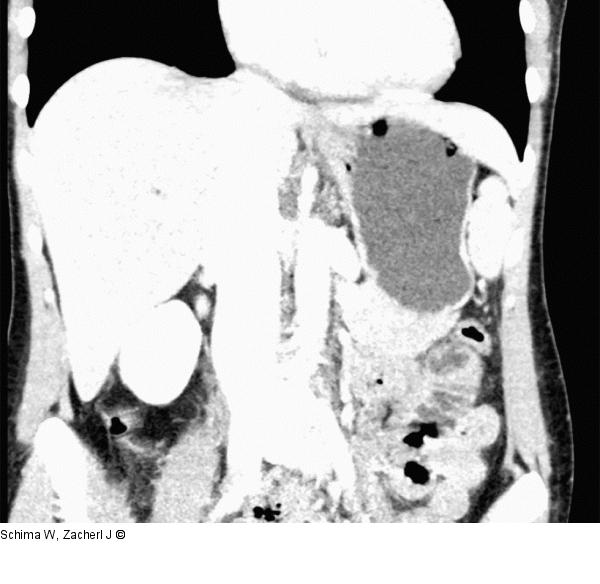

Abbildung 1: Antrum-Karzinom Die MDCT-Rekonstruktion in koronaler Ebene zeigt das Wand-überschreitende Antrum-Karzinom und die fetthältige Läsion zwischen Leber und rechter Zwerchfellkuppe, dem Pseudolipom entsprechend. |

Die MDCT-Rekonstruktion in koronaler Ebene zeigt das Wand-überschreitende Antrum-Karzinom und die fetthältige Läsion zwischen Leber und rechter Zwerchfellkuppe, dem Pseudolipom entsprechend. |